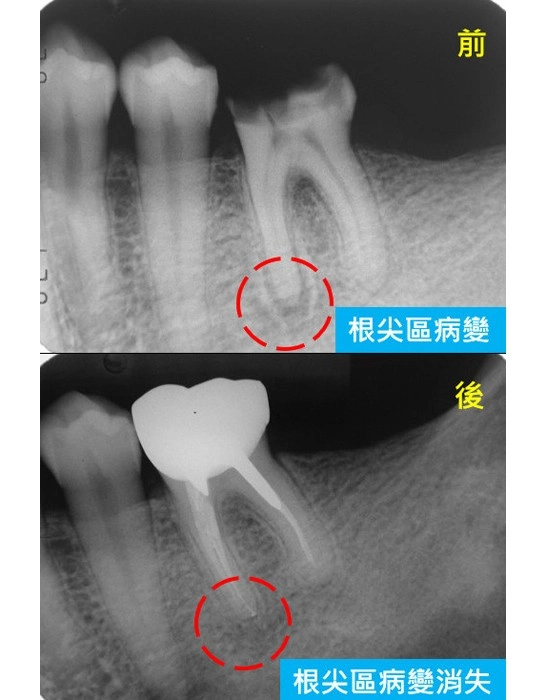

顯微根管-根尖區病變案例

顯微根管治療案例